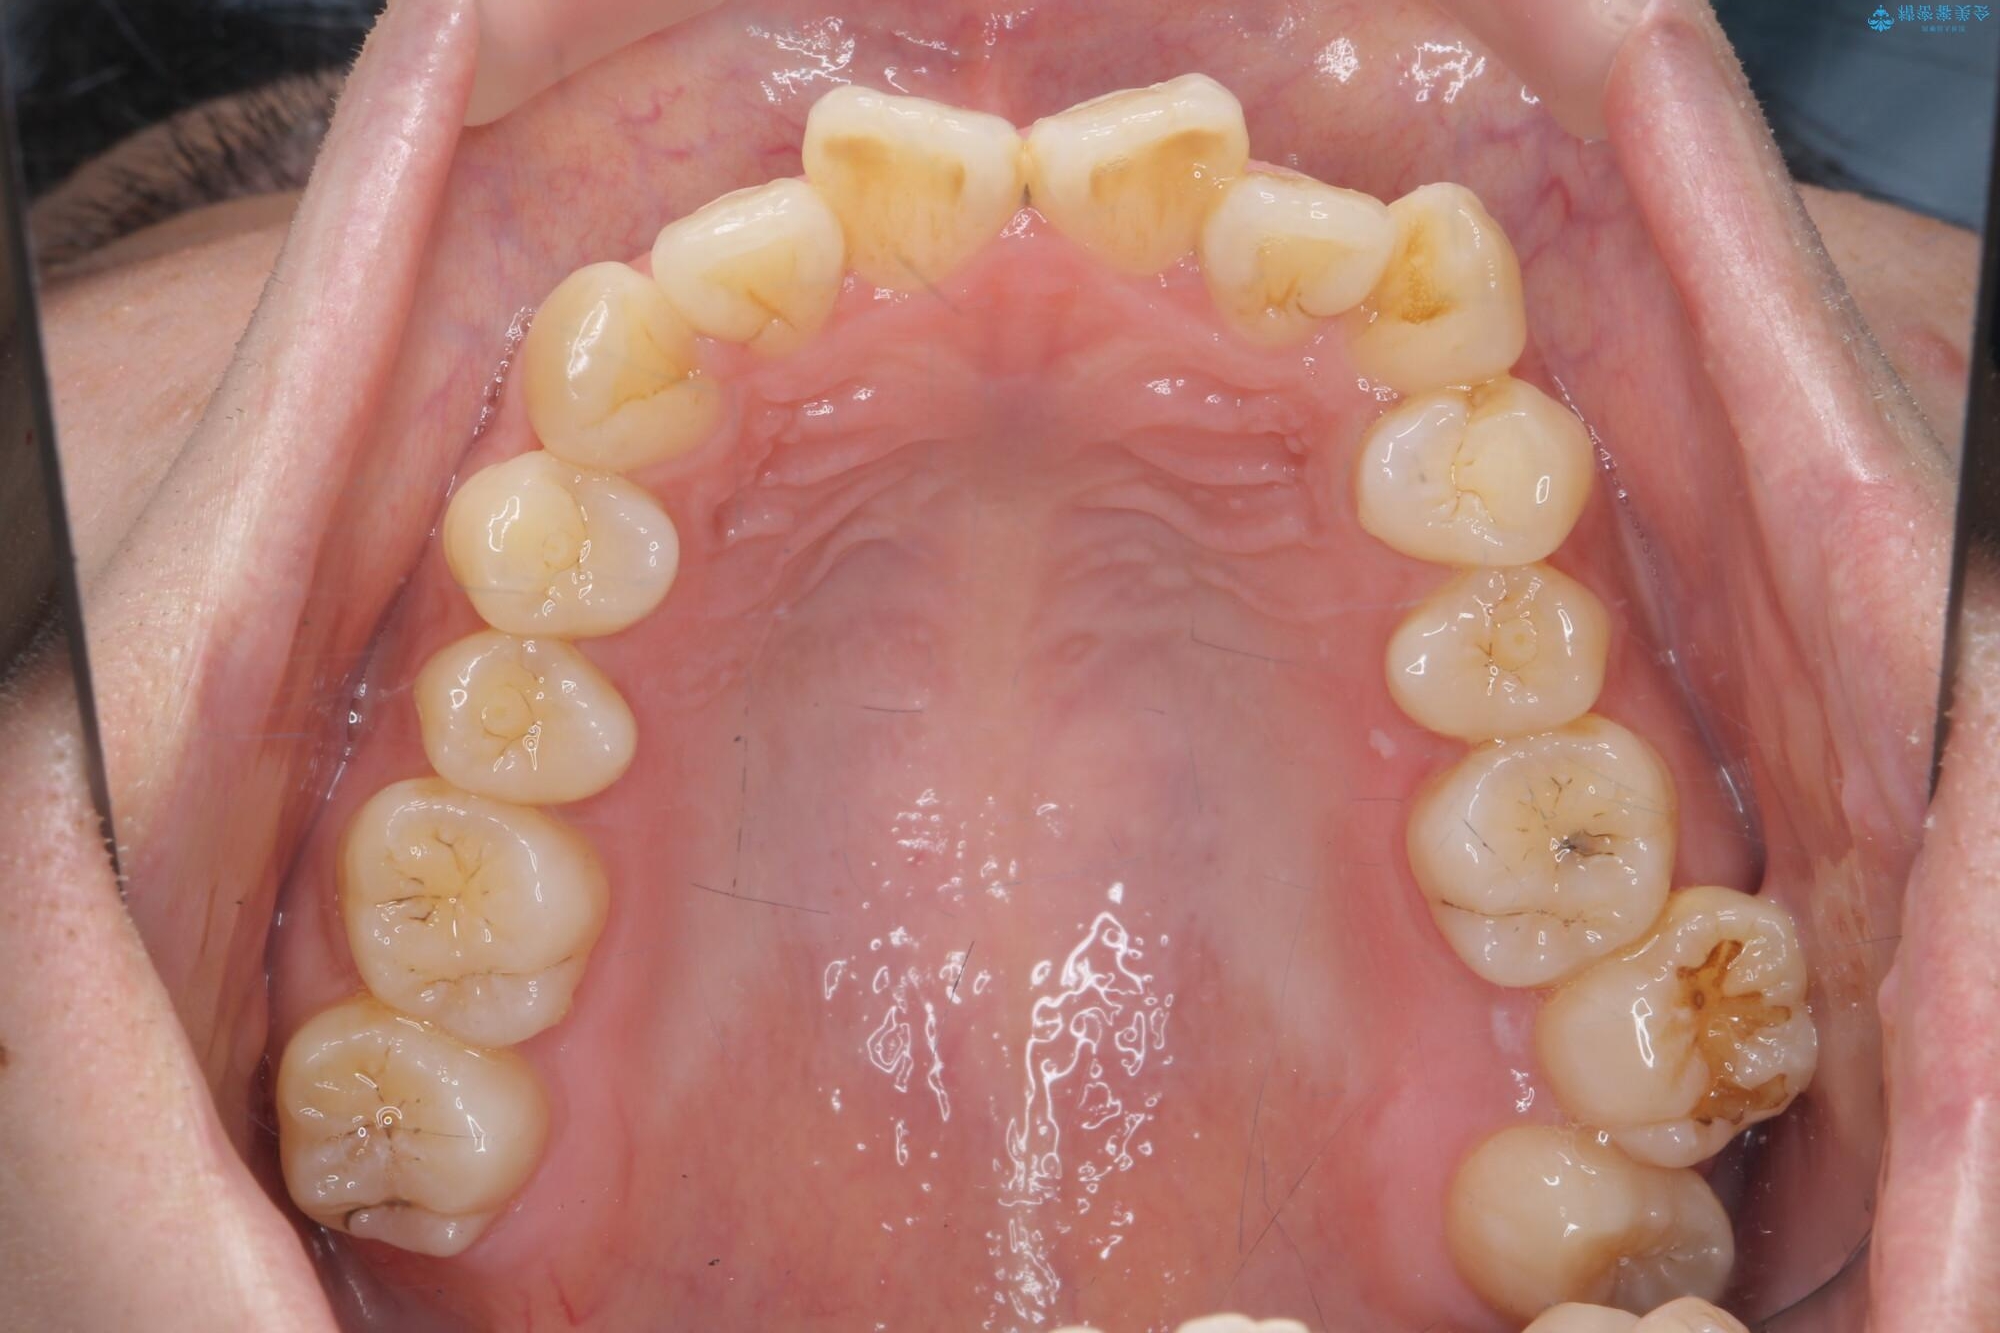

治療前

気になる犬歯のガタつきをマウスピース矯正で改善 治療前画像 気になる犬歯のガタつきをマウスピース矯正で改善 治療前画像 気になる犬歯のガタつきをマウスピース矯正で改善 治療前画像 気になる犬歯のガタつきをマウスピース矯正で改善 治療前画像